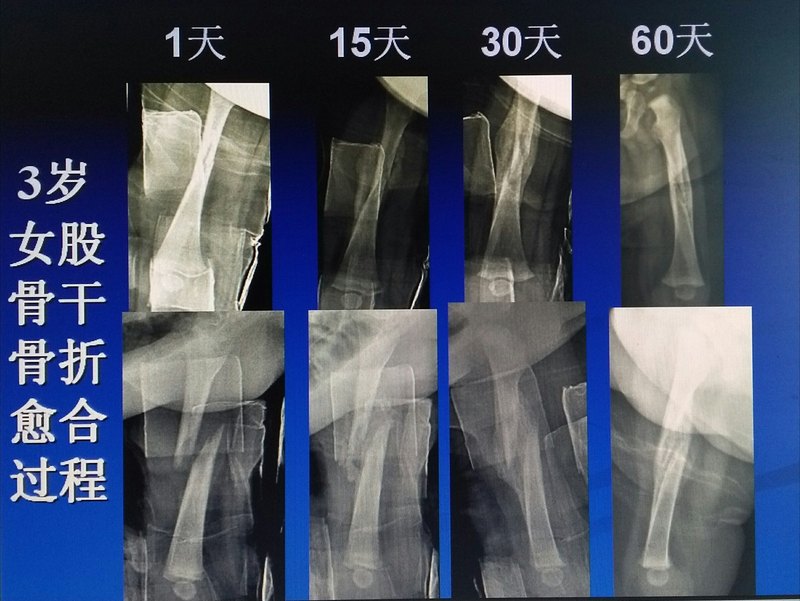

兒童骨折的治療不需要嚴(yán)絲合縫每個(gè)孩子都是家長(zhǎng)的寶貝,孩子受傷骨折了,家長(zhǎng)最焦慮擔(dān)心,都想用最好的辦法給孩子治療,不留后遺癥。這不但是家長(zhǎng)追究的,也是每個(gè)醫(yī)生所追求的,只有醫(yī)患共同努力才能達(dá)到最好的治療效果。 醫(yī)生不但要治好病,還要積極跟家長(zhǎng)們溝通,消除家長(zhǎng)們的困惑疑慮,叫家長(zhǎng)了解疾病,知道怎么治療,知道家長(zhǎng)怎么配合治療護(hù)理,孩子的飲食,鍛煉,恢復(fù)。 家長(zhǎng)最關(guān)注的問(wèn)題: 1.孩子受傷嚴(yán)重不嚴(yán)重 2.怎么治療,保守還是手術(shù) 3.手術(shù)怎么治療 4.治療后會(huì)不會(huì)留后遺癥 5.骨頭錯(cuò)茬影不影響 等等問(wèn)題。 兒童骨折的治療與成人骨折不同,兒童牽涉生長(zhǎng)發(fā)育,治療理念和方法都不同,兒童骨折不需要對(duì)的嚴(yán)絲合縫,只要力線好,骨折會(huì)自己修復(fù)塑形好的。 兒童骨折的治療原則: 兒童骨折治療首選保守,手術(shù)首選微創(chuàng),能簡(jiǎn)單不復(fù)雜,稀疏內(nèi)固定,堅(jiān)強(qiáng)外固定。